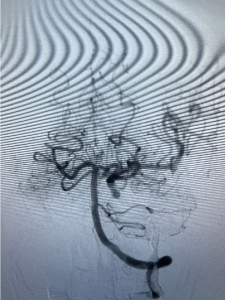

快速闭塞血管后无出血

后交通动脉开放 代偿左侧大脑中动脉供血

“患者左侧颈内动脉后交通动脉粗大,假性动脉近远端已经发生夹层改变。”手术团队凭借丰富的经验,果断决策闭塞左侧颈内动脉,选择大而长的弹簧圈在假性动脉瘤近远端闭塞颈内动脉,成功止住出血。取出咽喉部压迫棉片及棉条均无活动性出血,继续输血、输血浆,予以抗休克治疗。全脑血管造影显示,后交通动脉代偿良好,左侧大脑中动脉血流速度正常,眼动脉显影良好,患者的生命体征逐步恢复正常。见患者情况逐渐平稳,所有人都松了一口气。